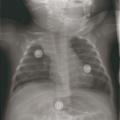

– atélectasie segmentaire ou lobaire en cas de bouchons muqueux (craindre une surinfection bactérienne) [fig. 2] ;